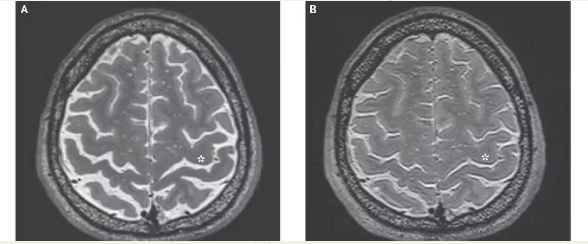

正常大脑(左)与长时间(4个月以上)

太空飞行的大脑对比